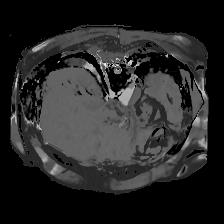

In clinical practice, well-aligned multi-modal images, such as Magnetic Resonance (MR) and Computed Tomography (CT), together can provide complementary information for image-guided therapies. Multi-modal image registration is essential for the accurate alignment of these multi-modal images. However, it remains a very challenging task due to complicated and unknown spatial correspondence between different modalities. In this paper, we propose a novel translation-based unsupervised deformable image registration approach to convert the multi-modal registration problem to a mono-modal one. Specifically, our approach incorporates a discriminator-free translation network to facilitate the training of the registration network and a patchwise contrastive loss to encourage the translation network to preserve object shapes. Furthermore, we propose to replace an adversarial loss, that is widely used in previous multi-modal image registration methods, with a pixel loss in order to integrate the output of translation into the target modality. This leads to an unsupervised method requiring no ground-truth deformation or pairs of aligned images for training. We evaluate four variants of our approach on the public Learn2Reg 2021 datasets \cite{hering2021learn2reg}. The experimental results demonstrate that the proposed architecture achieves state-of-the-art performance. Our code is available at https://github.com/heyblackC/DFMIR.

图像配准是图像处理研究领域中的一个典型问题和技术难点,其目的在于比较或融合针对同一对象在不同条件下获取的图像,例如图像会来自不同的采集设备,取自不同的时间,不同的拍摄视角等等,有时也需要用到针对不同对象的图像配准问题。具体地说,对于一组图像数据集中的两幅图像,通过寻找一种空间变换把一幅图像映射到另一幅图像,使得两图中对应于空间同一位置的点一一对应起来,从而达到信息融合的目的。 该技术在计算机视觉、医学图像处理以及材料力学等领域都具有广泛的应用。根据具体应用的不同,有的侧重于通过变换结果融合两幅图像,有的侧重于研究变换本身以获得对象的一些力学属性。